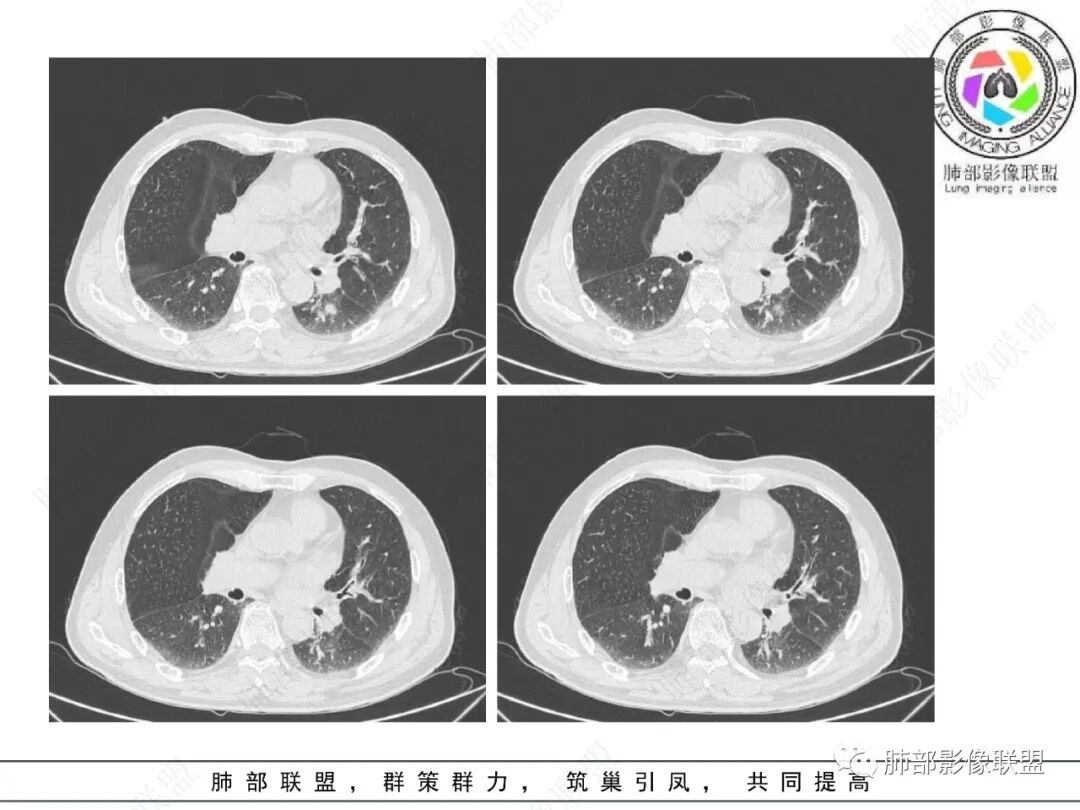

影像学表现:左肺下叶背段近叶间裂旁不规则实性密度结节影,图像未明确显示与支气管关系。边界清,整体膨隆感较明显,边缘显示分叶,偶见段毛刺,叶间胸膜“L”形牵拉凹陷,密度均匀,未见空洞或液化,也未见明显脂肪密度及钙化,轻到中度渐进性强化,未见明确蛇纹状血管应。左肺门可见多发小淋巴结影,纵隔内未见明显肿大淋巴结影。

未见明确卫星灶。